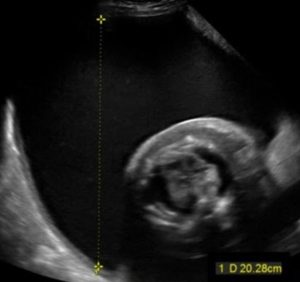

Cổ tử cung ngắn – Nguyên nhân, dấu hiệu và cách xử trí

Cổ tử cung ngắn là tình trạng chiều dài cổ tử cung, khi đo bằng [...]